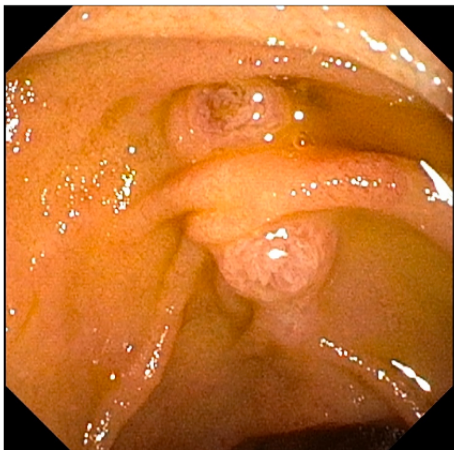

《Journal of the Canadian Association of Gastroenterology》近期报道了这样一个突破性病例:一位48岁女性患者因胆石症出现上腹痛、肝酶升高和高胆红素血症。在进行常规ERCP检查时,内镜医师意外发现了令人惊讶的景象——十二指肠腔内竟然并列存在着两个壶腹部隆起。

患者临床表现为典型的胆道梗阻症状。ERCP检查中发现两个独立的壶腹部隆起,上位壶腹成功插管后完成乳头切开术,并通过球囊导管清除胆总管结石。后续MRCP检查显示患者存在胰腺分裂症变异,主胰管主要延续至预期副乳头位置,而主胰管的一个较小分支延伸至壶腹区域,但在胆总管末端下方终止,未形成两者汇合。